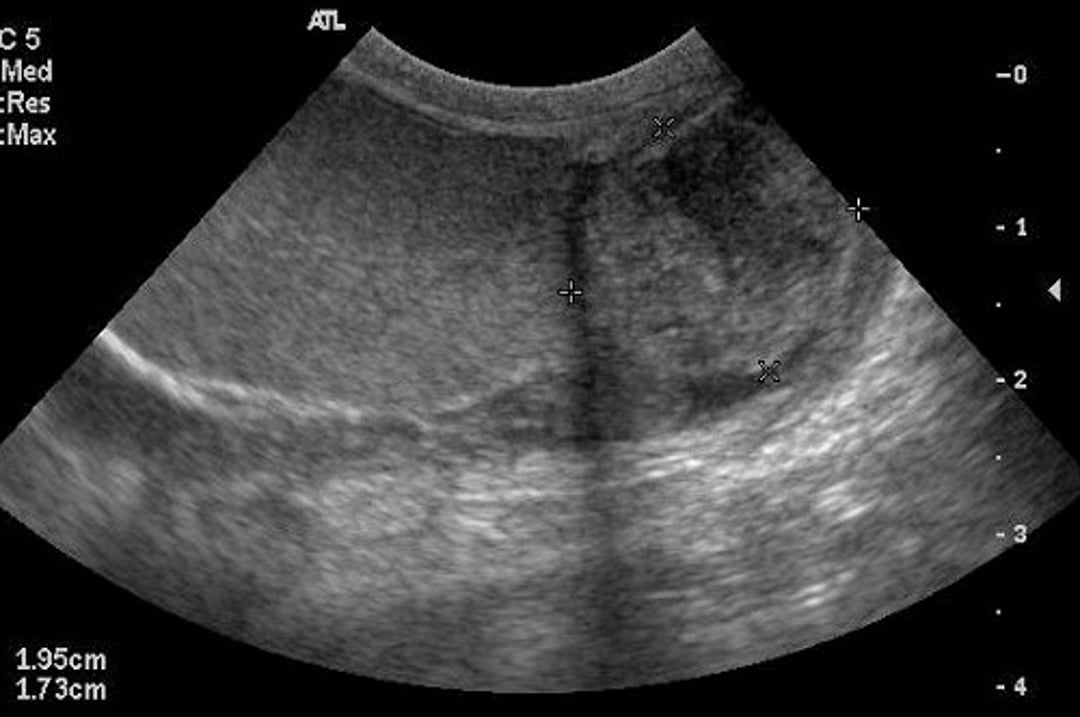

Ecografía transversal del escroto de un perro con epididimitis crónica. Observe el epidídimo agrandado (cuatro cursores), que tiene una ecogenicidad mixta.

Cortesía de la Dra. Autumn Davidson.